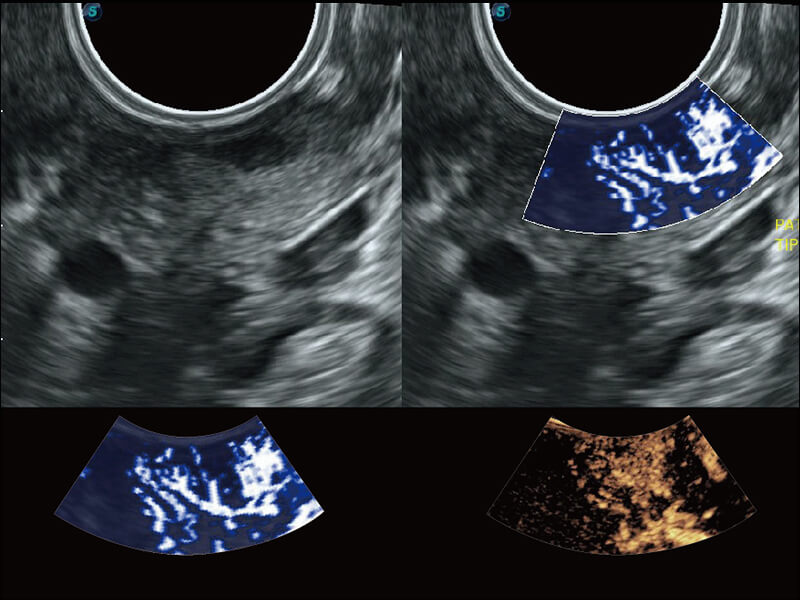

S60探头工艺,从前端信号处理每一个环节采集无损声学数据,真实还原组织原貌,再现解剖细节。